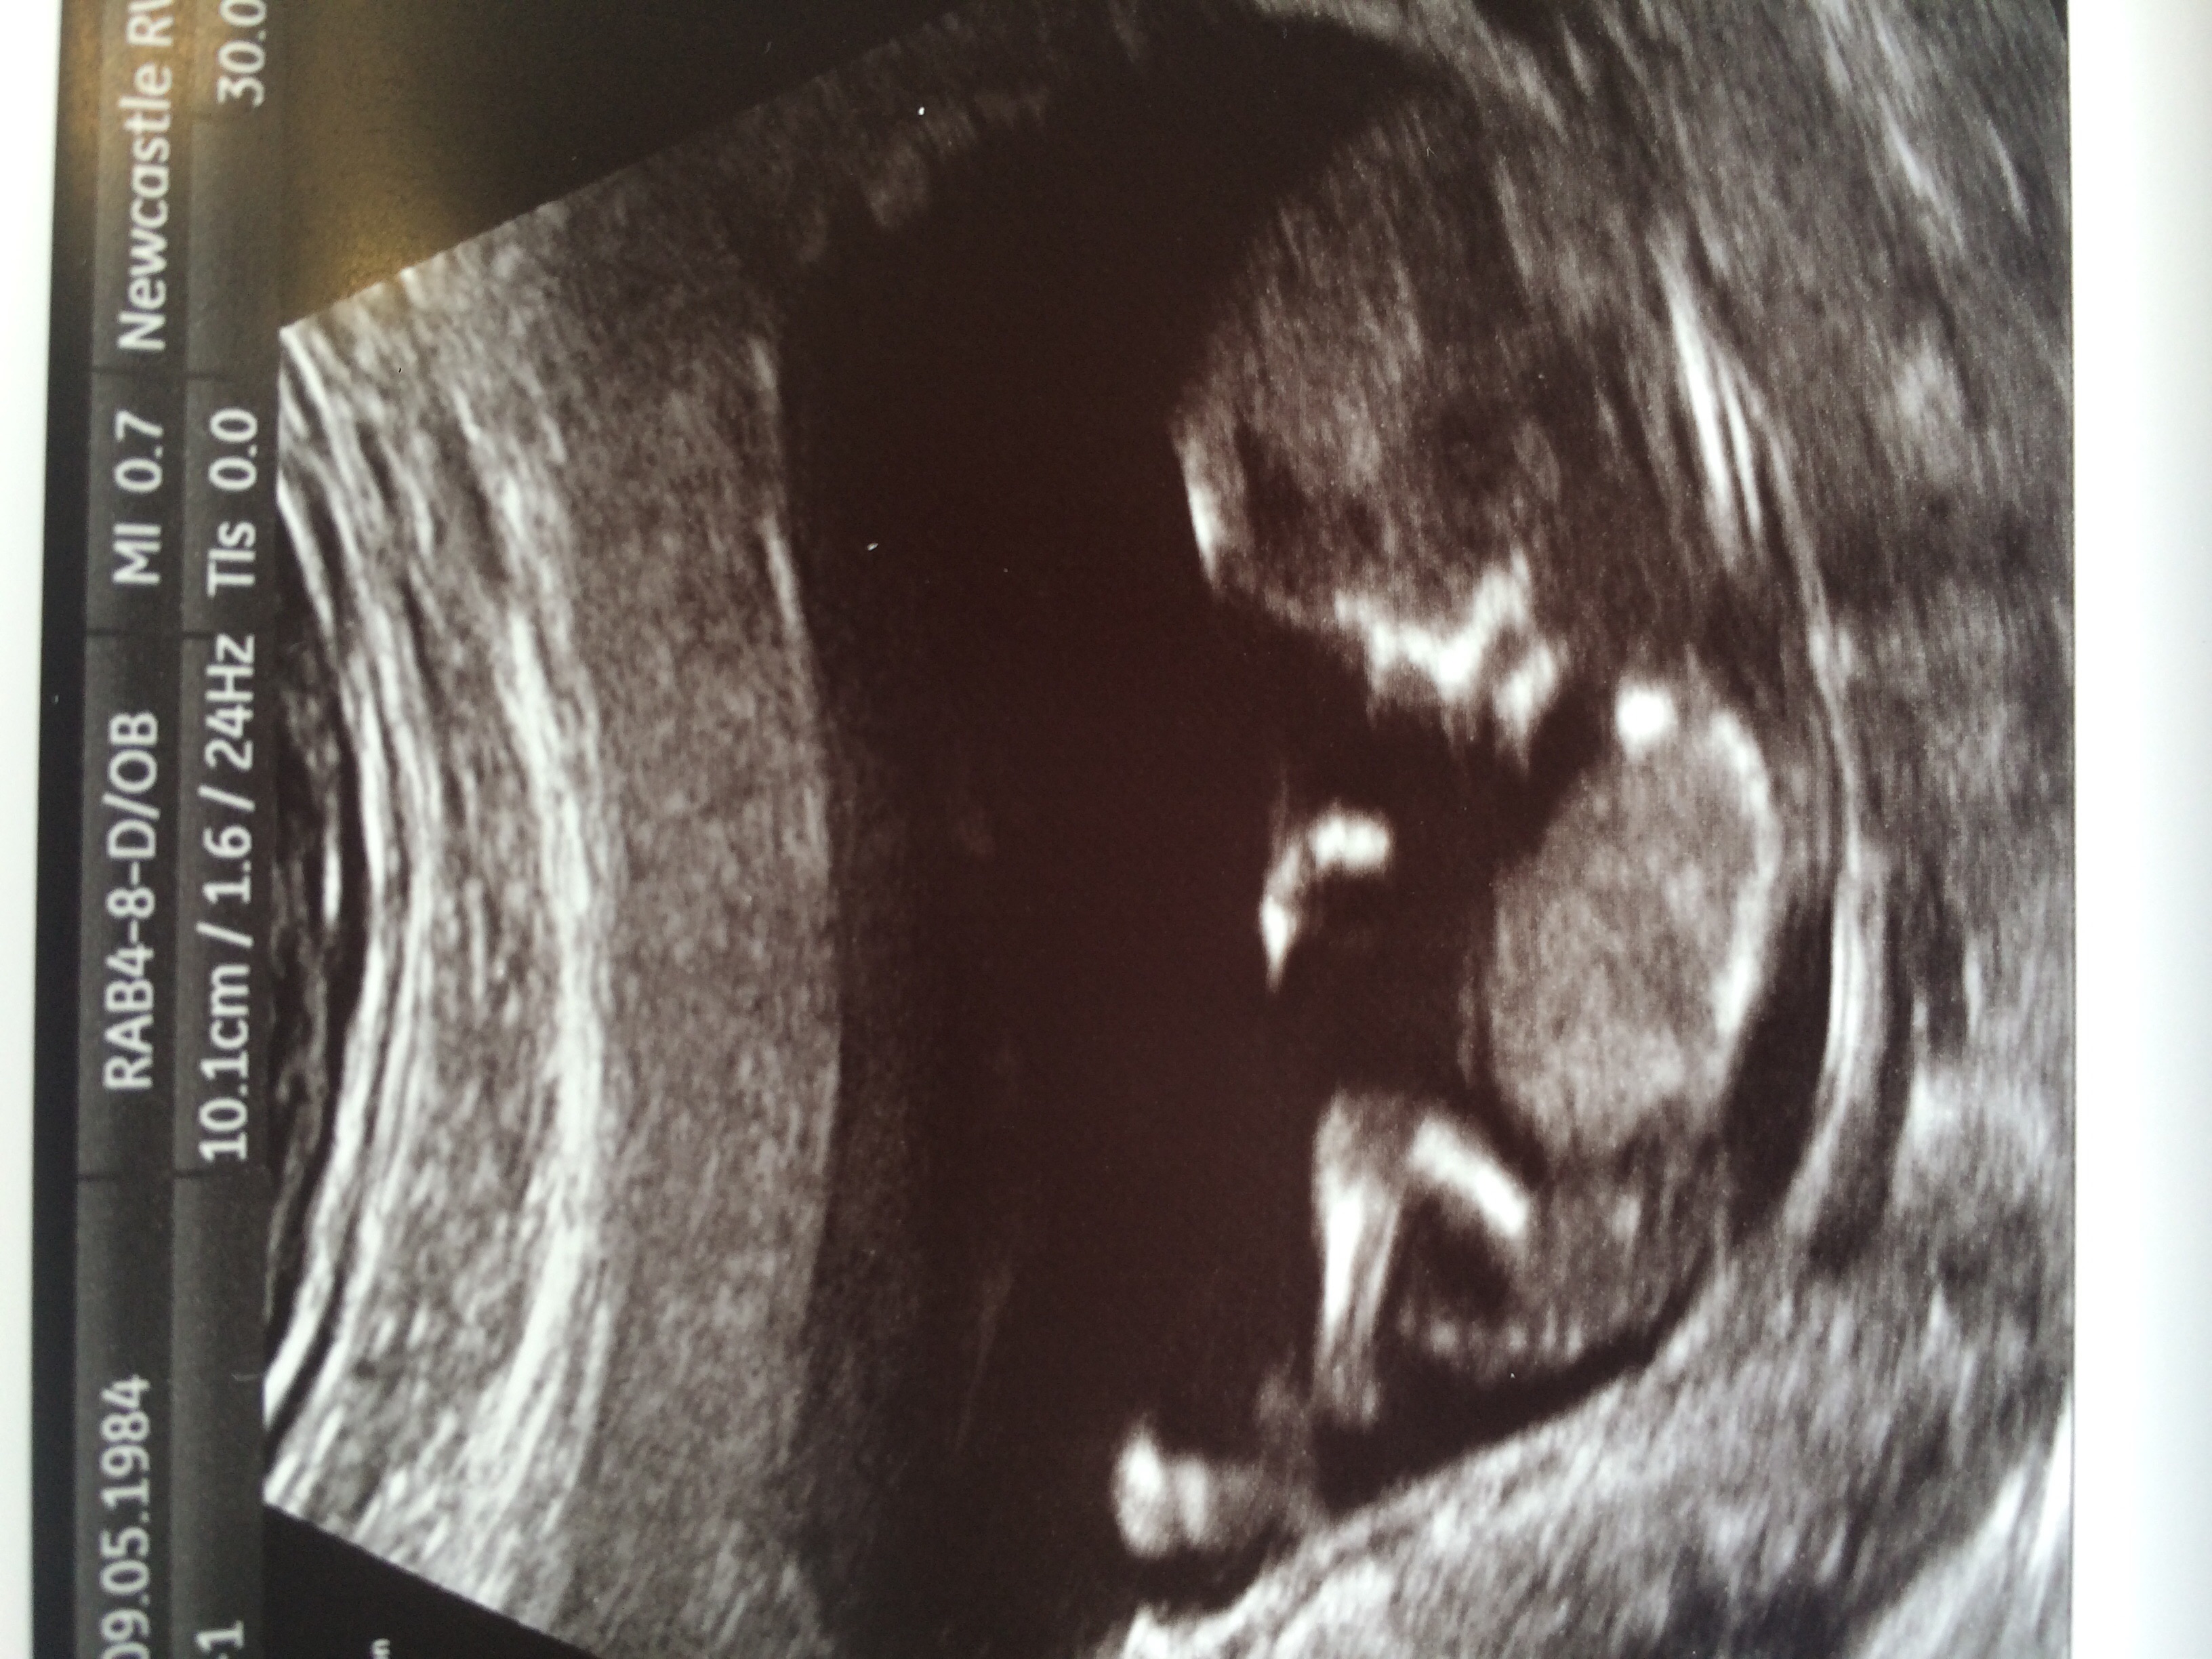

Had my scan today. I'm 12+5. Can you please give your guesses. You were spot on with my first baby.

Here is the picAttachment 25925Attachment 25925